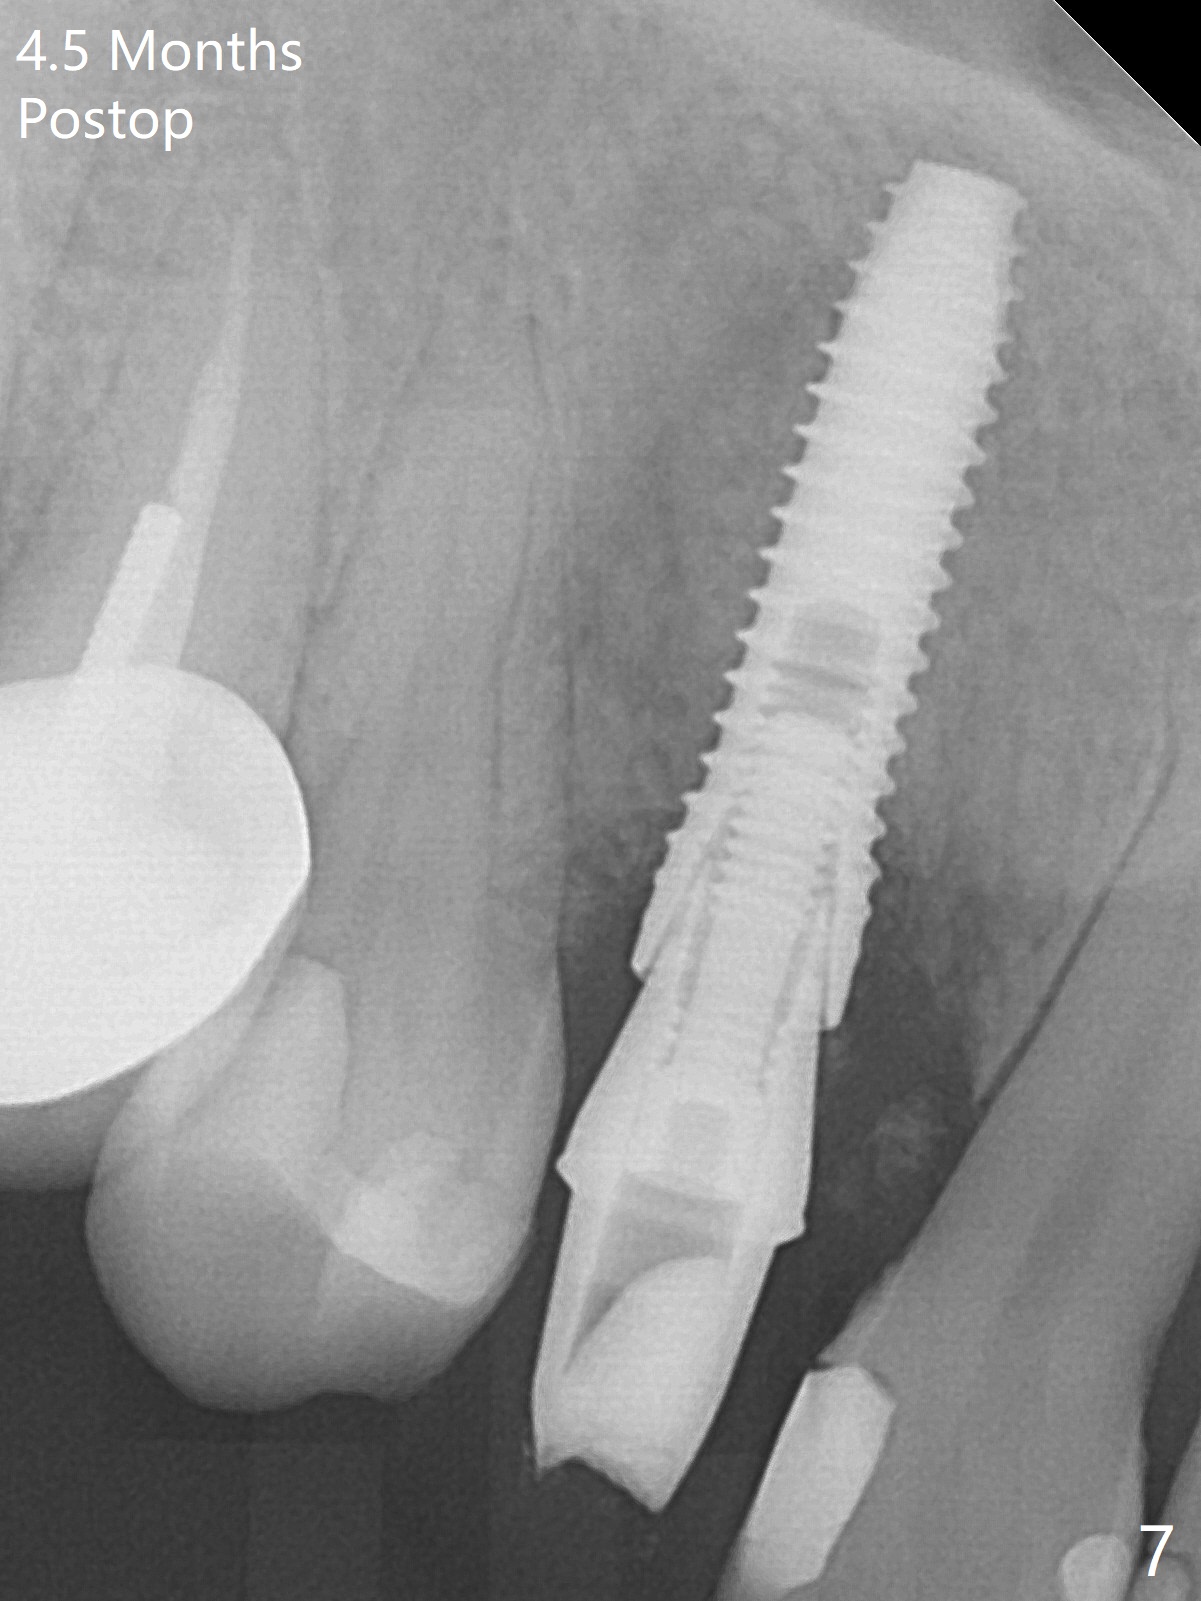

When the tooth #6 with loose crown and post (Fig.1) is extracted, there is no granulation tissue in the socket with the thin intact buccal plate. As planned, osteotomy is initiated in the mesio-palatal slope of the socket (Fig.2 red dashed line). After osteotomy for 3x20 mm (gingival level), a 3.8x15 mm dummy implant is placed partially (Fig.3 D). A final implant with the same dimension is placed with > 50 Ncm (Fig.4). Before and after placement of a 4.5x5(3) mm abutment, Vera graft is placed in the remaining socket space (mainly buccal, Fig.5 *). As routine, an immediate provisional is fabricated with occlusal clearance. The gingiva looks healthy around the provisional 1 week postop (Fig.6 P). Adjust and polish the mesioocclusal composite at #5 if necessary before impression. The bone graft appears to remain in place 4.5 months postop (Fig.7). A bevel buccal subgingival margin is placed prior to impression. The bone density around the coronal portion of the implant increases 9 months postop (4 months post cementation, Fig.8). There is no gingival erythema or edema around the implant crown at #6 ten months post cementation (Fig.6, as compared to preop condition and that of the neighboring crown (*)). Both the buccal and palatal plates are thin or absent 1 year 5 months post cementation (Fig.10,11, as compared to Fig.12 for the tooth #11 (thin buccal bone)). Socket shield should be done with a smaller implant.